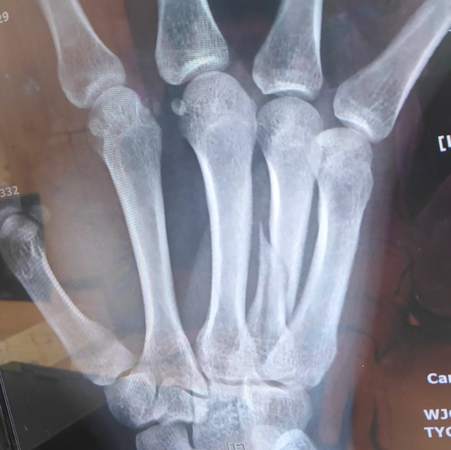

盧學叡11日在Instagram曬出手掌處的X光照,照片中可以看到他的掌骨明顯裂開,他無奈在內文寫下「2025(年)應該就會開始順利到不行了吧!」透露10日睽違半年回到排球場打球,卻不慎打到骨折,自嘲「獲得一件新裝備」,向粉絲、好友們表示「目前會包著新裝備表演,大家不要嚇到了,希望快快跟裝備說掰掰!」

▲盧學叡的手掌X光片。(圖/翻攝自盧學叡Instagram)